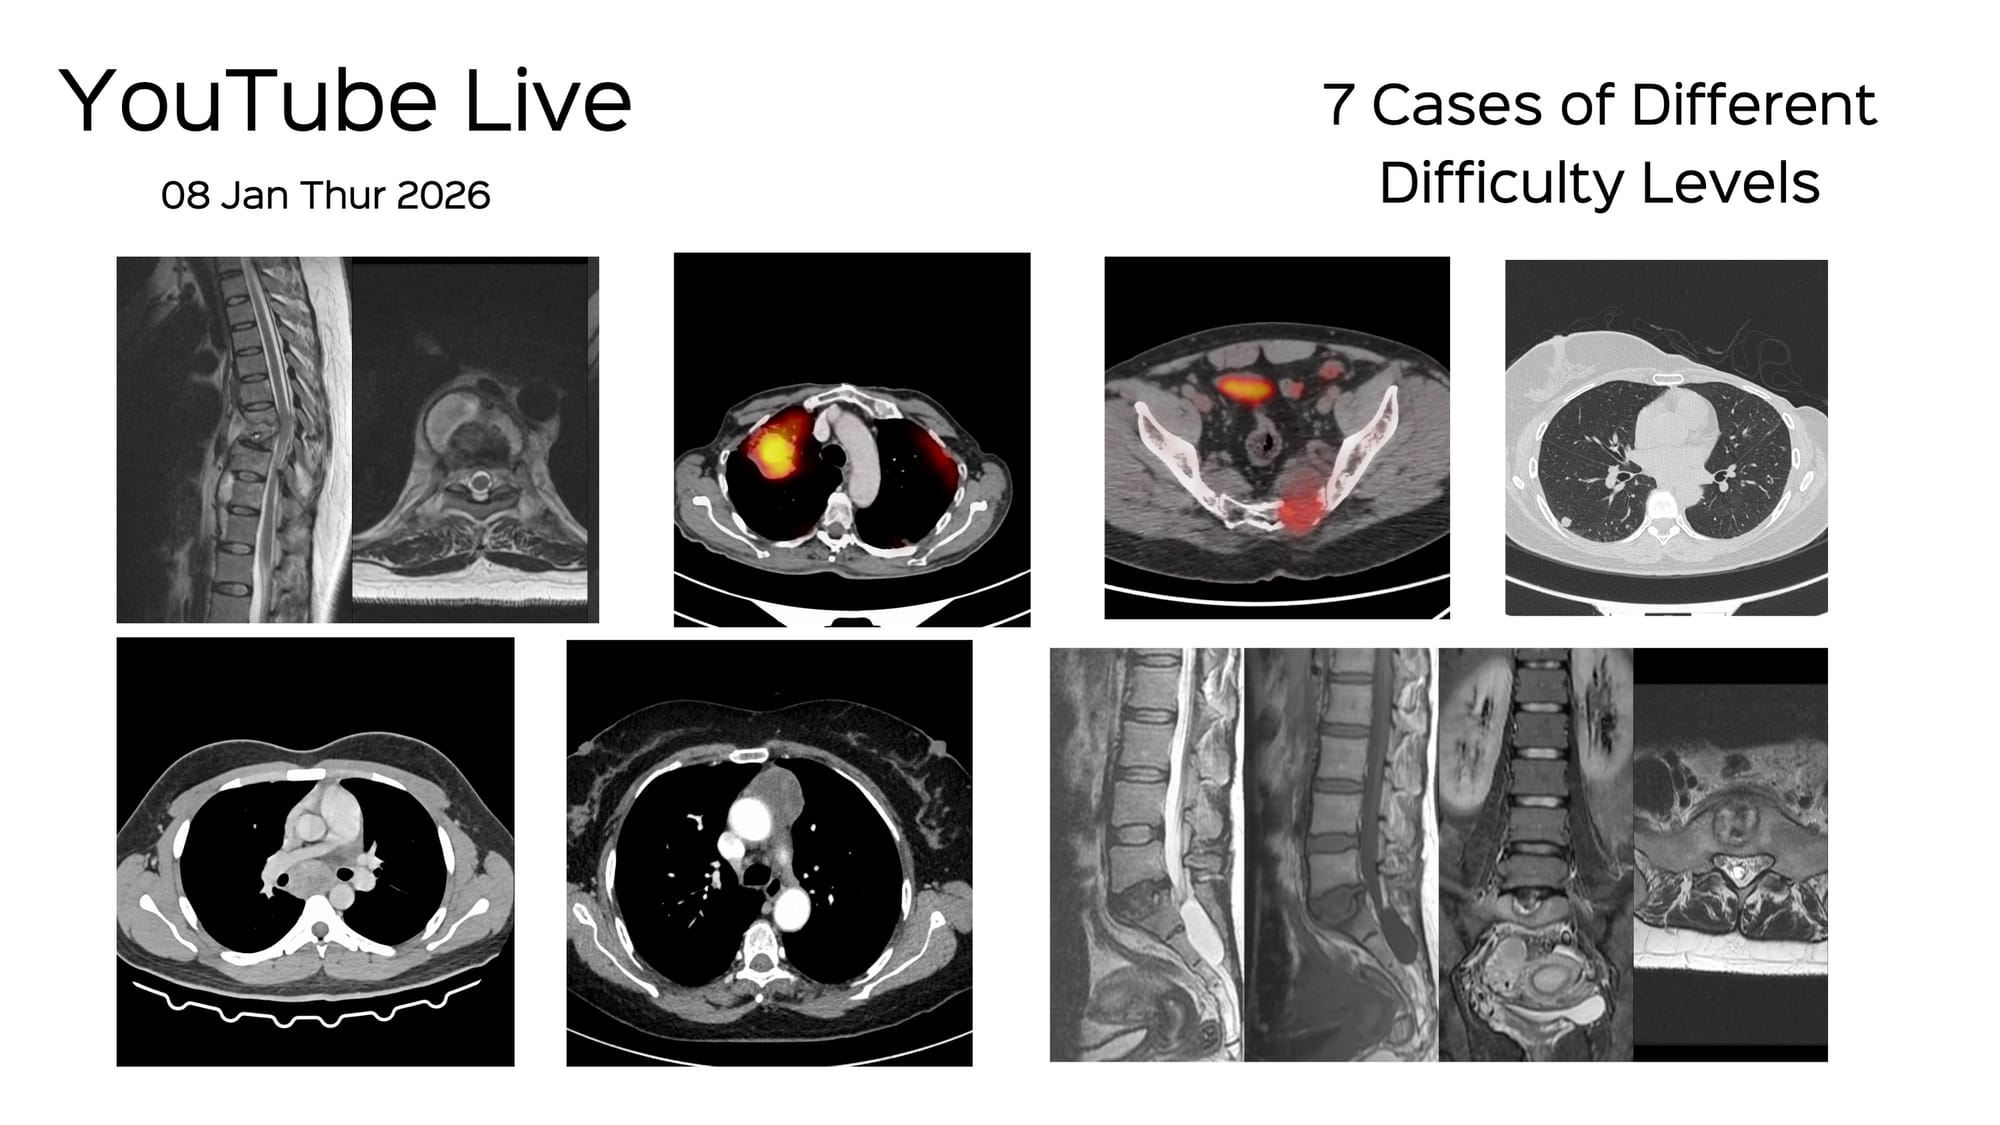

The 7 Cases for YouTube Live on 08 Jan at 7 PM Indian Standard Time

Bhavin Jankharia - 04 January 2026